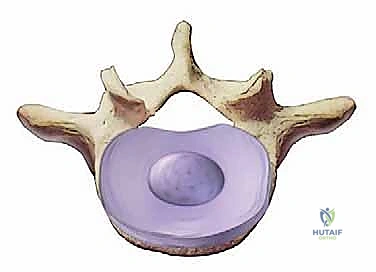

تتكون كل قطعة فقرية من:

1. الجسم الفقري (Vertebral Body): الكتلة العظمية الأسطوانية الكبيرة في الجزء الأمامي من الفقرة، وهي التي تتحمل الضغط.

2. القرص بين الفقرات (Intervertebral Disc): يعمل كوسادة لامتصاص الصدمات بين الأجسام الفقرية. يتكون من:

* الحلقة الليفية (Annulus Fibrosus): الغلاف الخارجي القوي والمرن.

* النواة اللبية (Nucleus Pulposus): المركز الهلامي الناعم الذي يوفر خاصية امتصاص الصدمات.

3. القناة الشوكية (Spinal Canal): الممر الذي يمر من خلاله الحبل الشوكي وجذور الأعصاب (ذنب الفرس في المنطقة القطنية).

4. المفاصل الوجيهية (Facet Joints): مفاصل صغيرة في الجزء الخلفي من العمود الفقري توجه وتحد من حركة الفقرات.